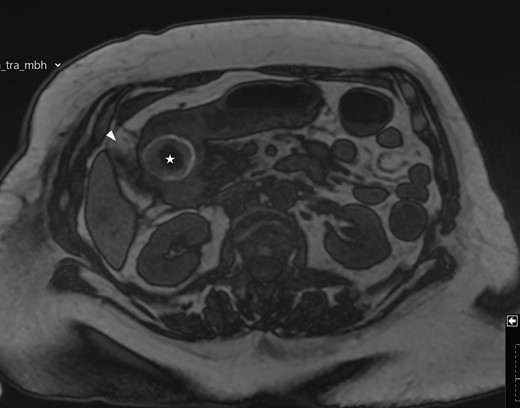

A frail 83-year-old female attended the emergency department with epigastric pain, vomiting and signs of sepsis with a heart rate of 101 and a temperature of 38°C. She had a recent admission with severe cholecystitis that was managed conservatively with intravenous antibiotics. On examination, she had tenderness in the right upper quadrant. Blood revealed an acute kidney injury, a CRP of 189 with normal liver function tests. Axial imaging demonstrated aerobilia with a dilated common bile duct of 14 mm and there was a 3.5 cm stone impacted in the first part of duodenum with evidence of a cholecysto-duodenal fistula (Figs 1–3).

MRI scan showing the gallbladder adherent to the duodenum with an impacted stone in the duodenum.